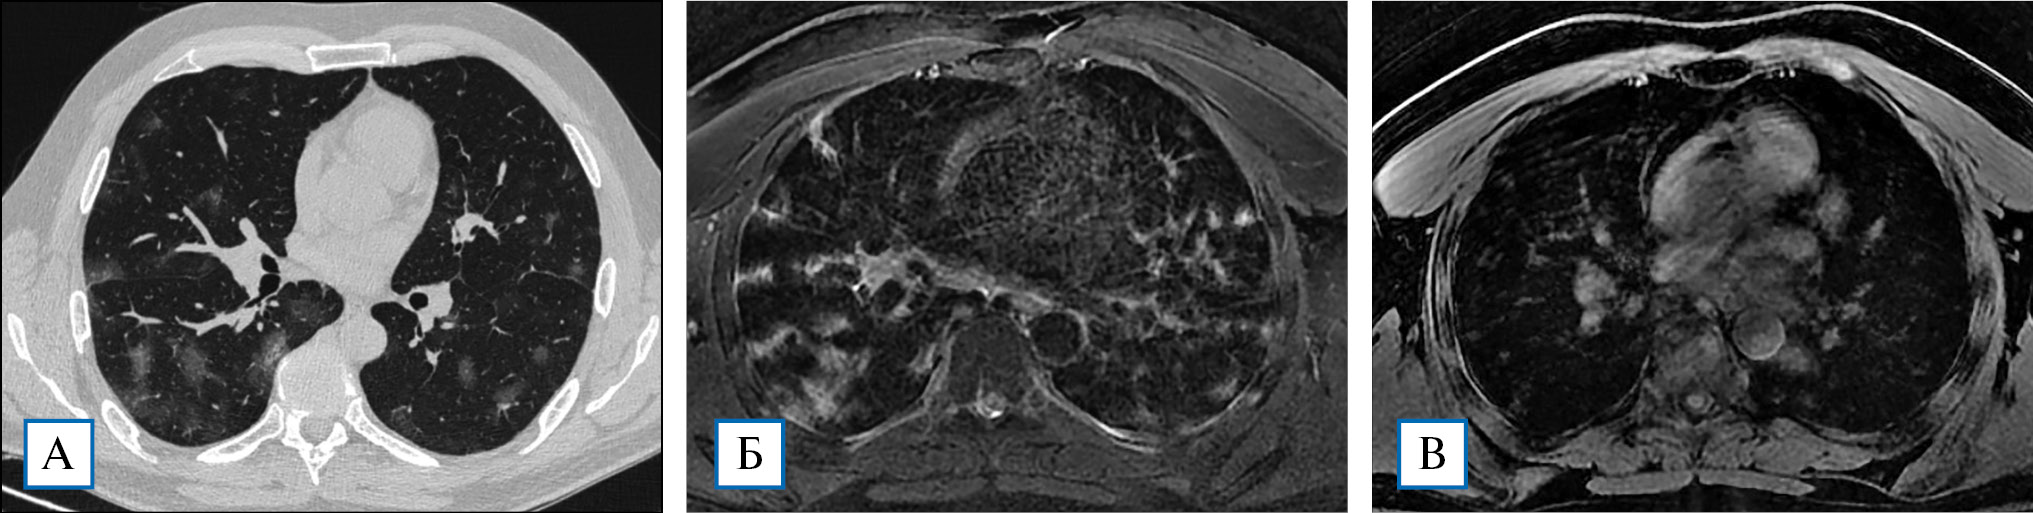

Рис. 3. Пациентка, 51 год, по данным КТВР в S6 правого легкого визуализируется обширная зона «матового стекла», переходящая в консолидацию, на фоне которой регистрируются ретикулярные изменения, представленные утолщенным внутридольковым интерстицием, что хорошо видно как на КТВР-срезах, так и на Т2-ВИ (А, Б, стрелки). Кроме того, Т2-ВИ позволяют уверенно выявлять утолщения интерстиция по ходу сосудов, отдельных междольковых перегородок — короткие стрелки). Т٢-последовательности дают возможность четко дифференцировать увеличенные лимфатические узлы (Б, треугольная стрелка). Т1-ВИ не позволяет визуализировать в полной мере как изменения в паренхиме, так и интерстициальные проявления поражения легких (В)

Рис. 4. Т2-ВИ МРТ имеет заметные преимущества в сравнении с КТВР в выявлении небольших объемов жидкости в плевральных полостях. Малый двусторонний гидроторакс у пациентки Б., 69 лет (стадия КТ1), уверенно выявляется на Т2 МРТ (стрелки, А) и практически не отображается на КТВР-срезах (Б)